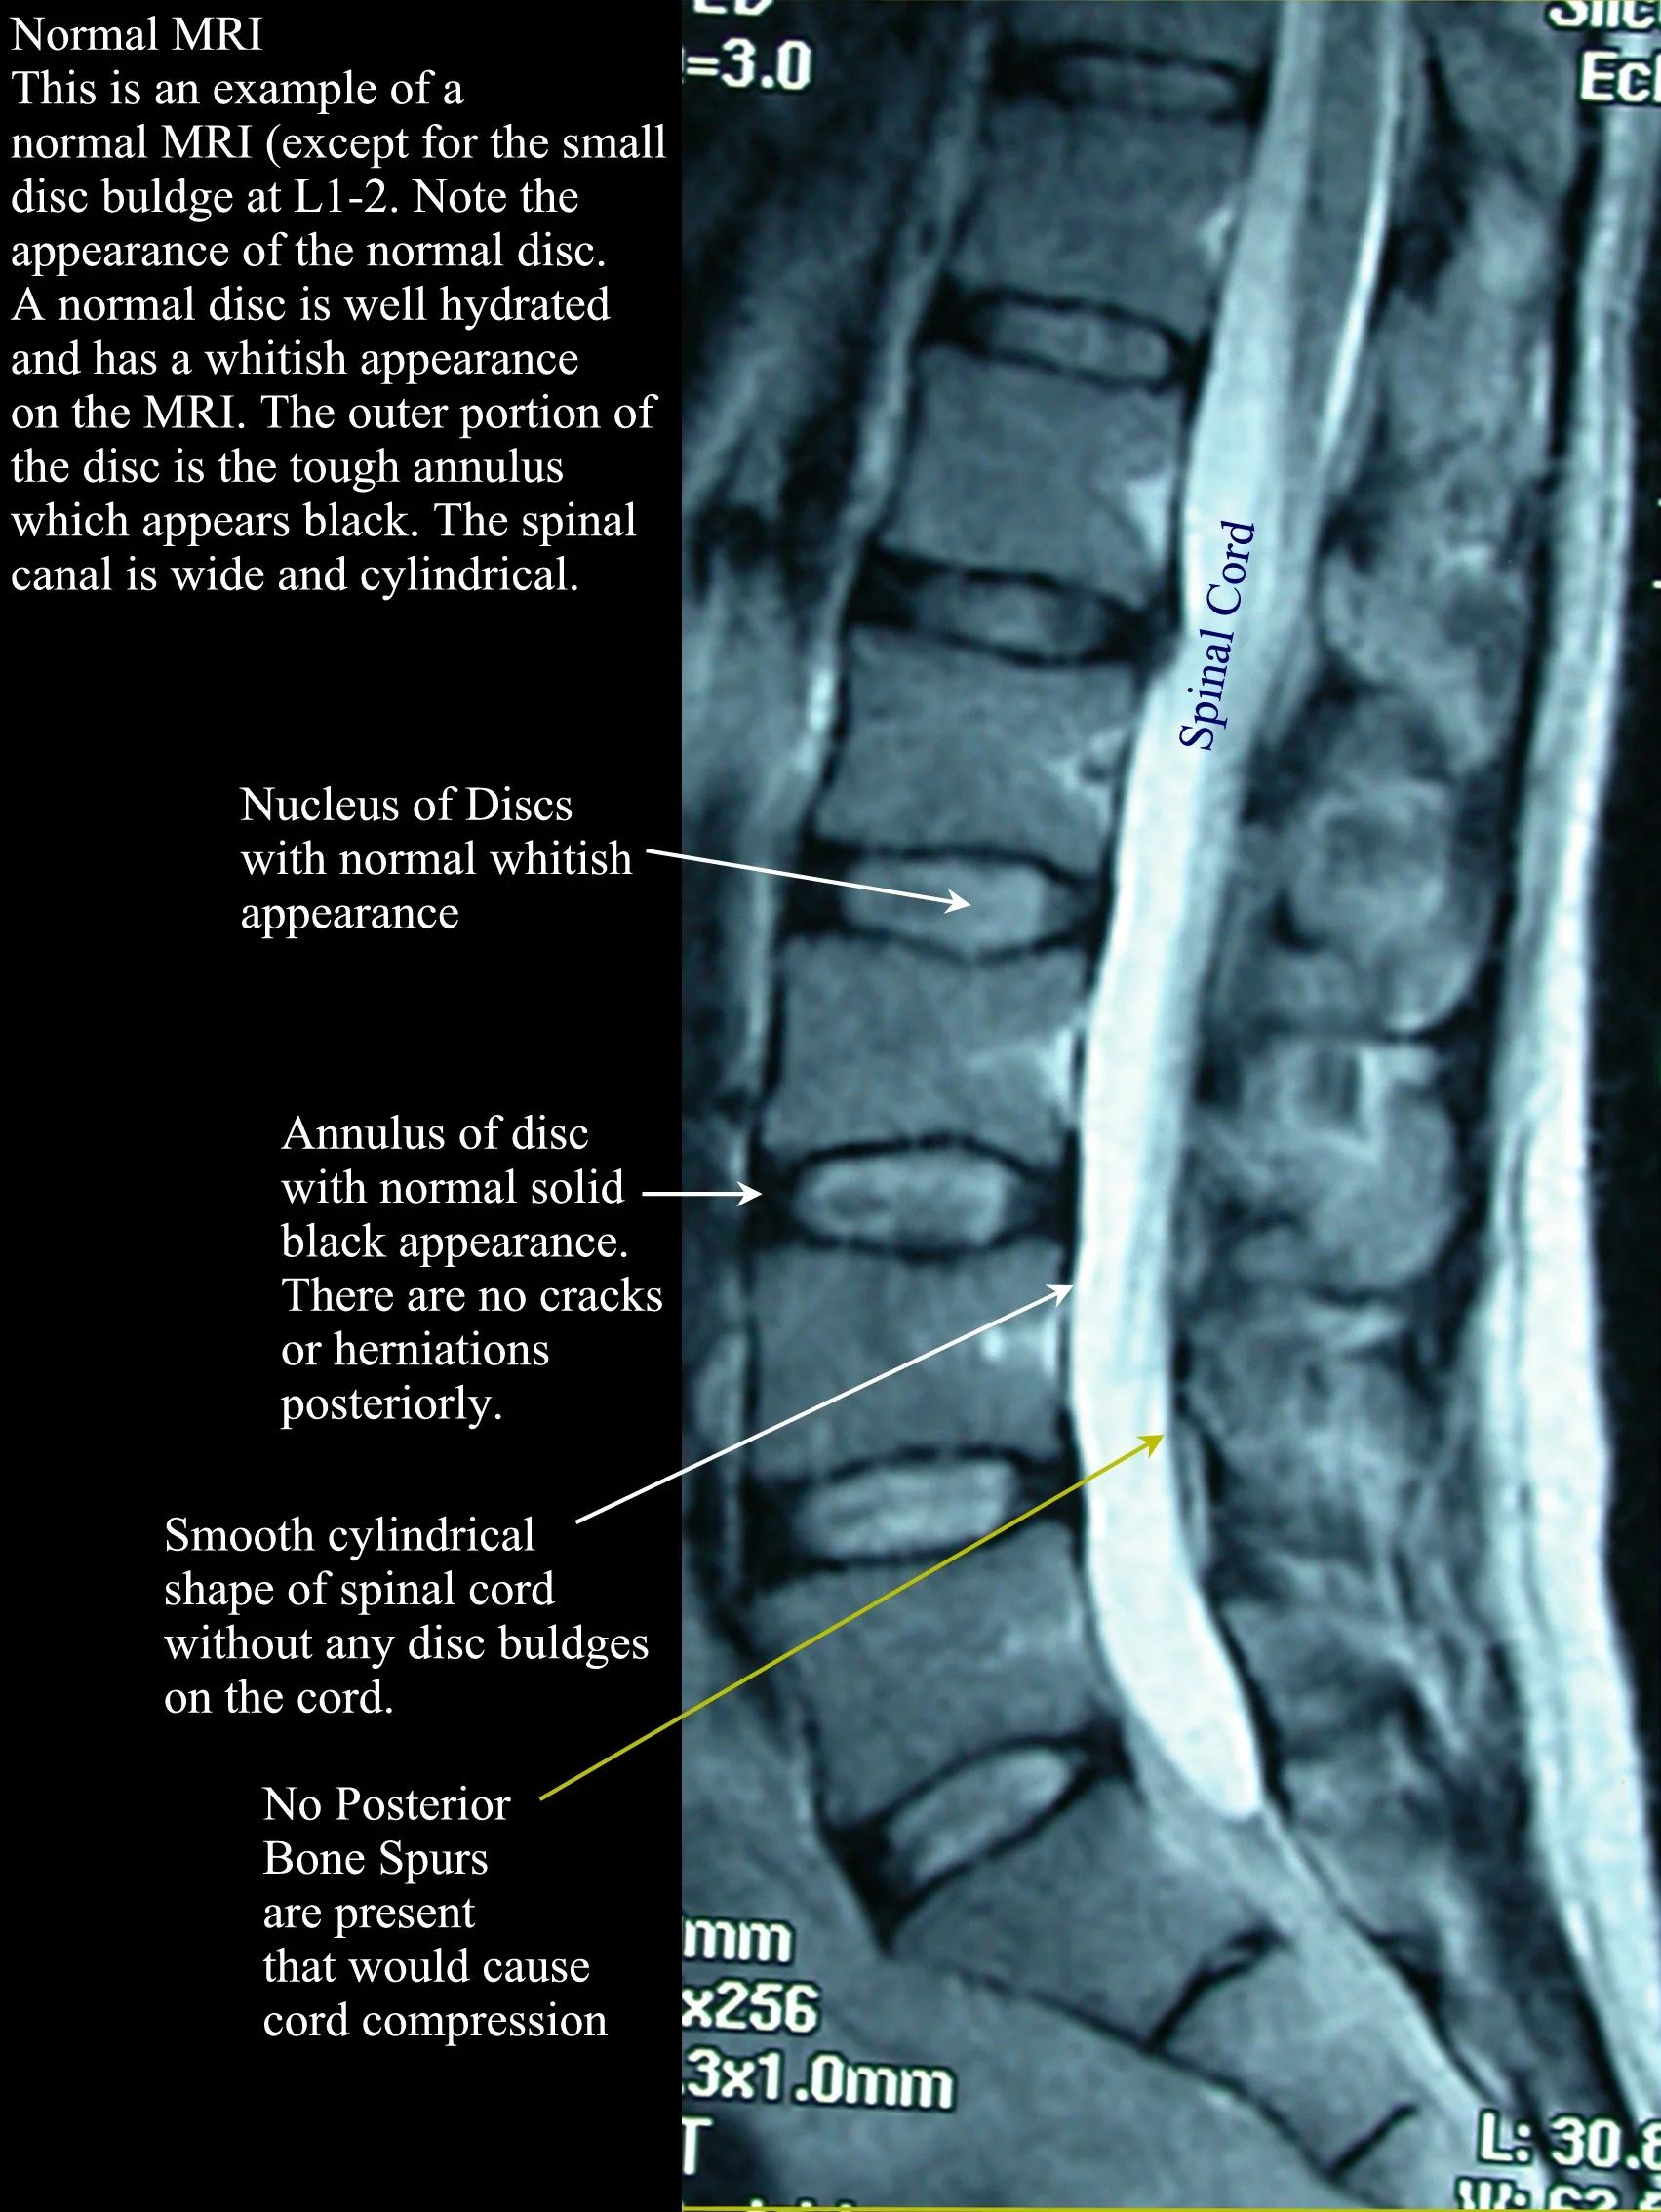

lumbar normal sag mri w text Mri, Mri technologist, Mri scan What Is A Mri Spine Lumbar a lumbar magnetic resonance imaging (mri) scan uses energy from strong magnets to create pictures of the lower. a lumbar mri is a powerful diagnostic tool that doctors may use to: in the spine, an mri scan can reveal thorough details of the joints, muscles, tendons, ligaments, spinal discs, spinal nerve roots, and. magnetic resonance imaging. What Is A Mri Spine Lumbar.